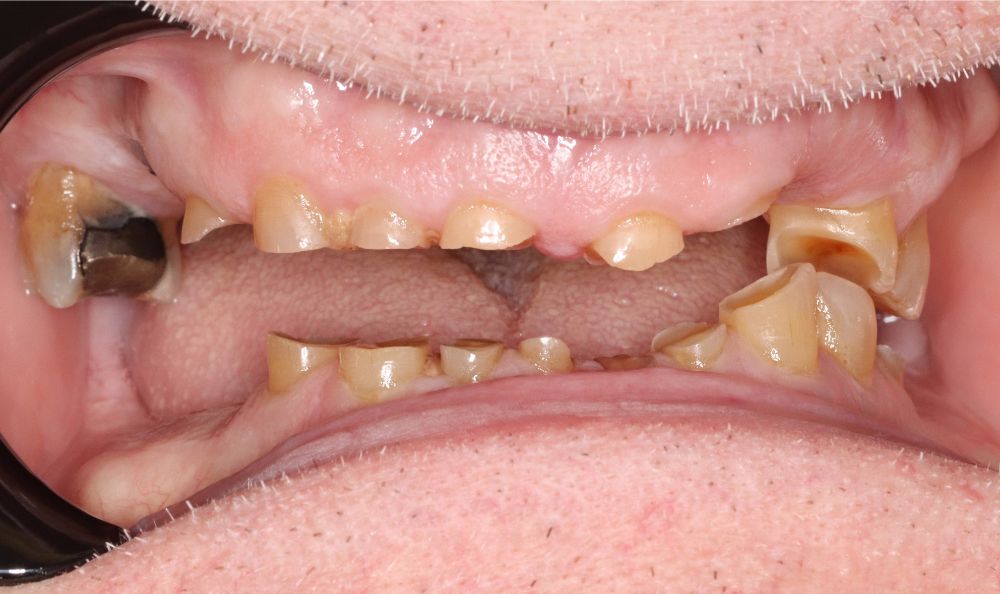

Jim came to our Anchorage dental office after years of living with worn-down, missing, and chipped teeth that had severely impacted his quality of life. Years of clenching and grinding had left his teeth damaged, difficult to use, and nearly invisible when he smiled. Simple pleasures, like enjoying a meal, laughing with friends, or showing his smile, had become sources of frustration and self-consciousness. But with Dr. Crosby’s help, Jim was ready to reclaim his smile, health, and confidence.

After a thorough evaluation, Dr. Crosby developed a comprehensive treatment plan to address Jim’s specific needs and restore his smile. The team began with a full mouth reconstruction. This process included extracting all remaining damaged teeth and strategically placing six implants on the upper arch and six on the lower. These implants now support a customized upper and lower hybrid denture, giving Jim a stable, beautiful, and fully functional smile.